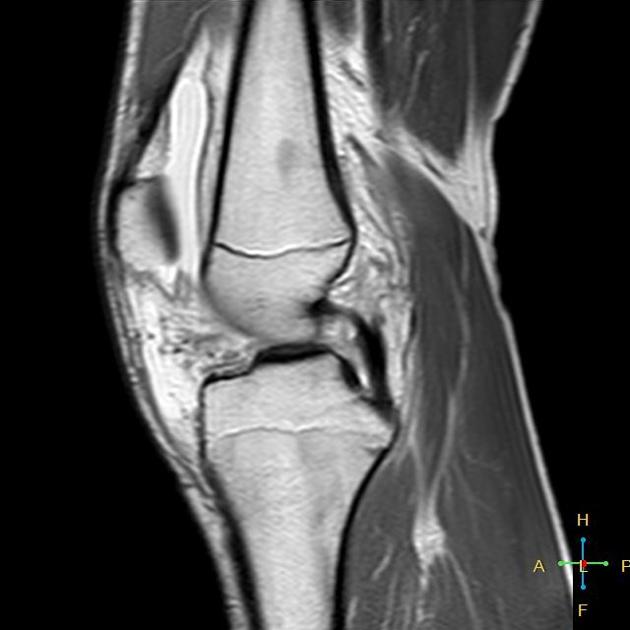

Dial Test / Loomer Test Posterolateral Rotatory Instability of the